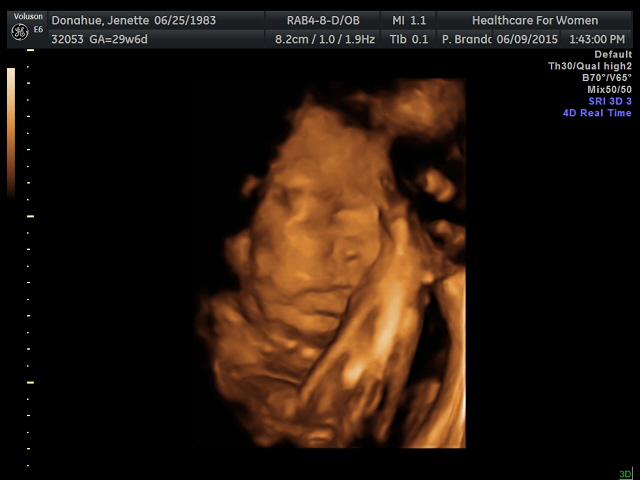

Share your 3D pics!!!!